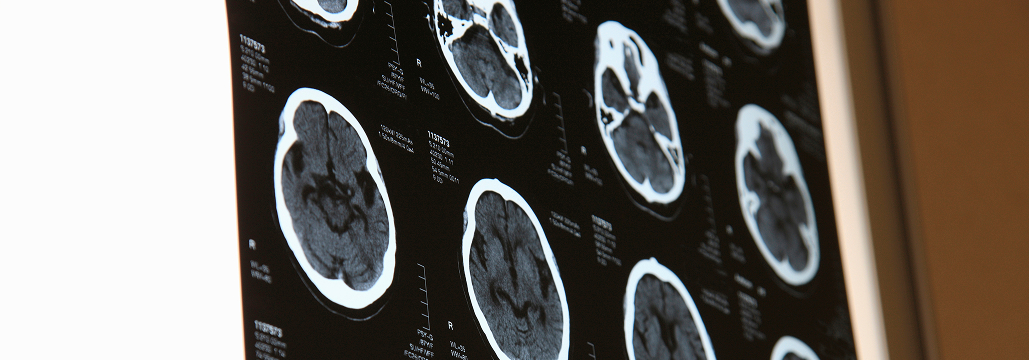

Akersらは、 脳および脊髄の海綿状血管奇形 (CM) の診断および臨床管理に関するエビデンスに基づくガイドライン更新を目的として、 系統的文献レビューと専門家コンセンサスに基づく検討を行った。 2014年10月~2023年3月に発表された文献234報を精査し、 疫学、 遺伝、 画像診断、 外科的治療、 神経学的管理の5領域について評価した。 その結果、 Delphi法により全会一致で53項目の管理推奨が策定された。 推奨の内訳はClass Ⅰが34%、 Class Ⅱが58%であり、 エビデンスレベルはLevel Aが6%、 Level Bが36%、 Level Cが58%だった。 本ガイドラインはCM診療の標準化に寄与する一方、 依然としてエビデンスレベルが低い項目が多く、 今後の研究の重要性が示された。